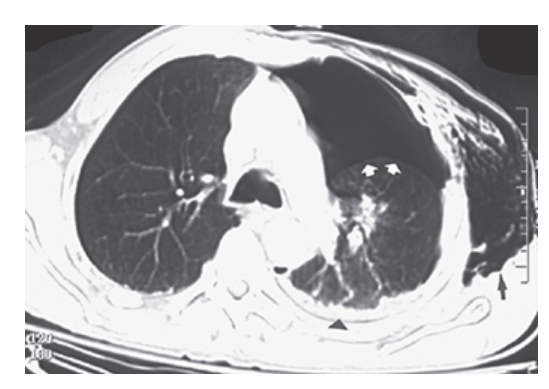

Pneumothorax. Contrast CT of the chest shows large left pneumothorax with air outlining the visceral pleura (short arrows). There is minimal hemothorax (arrowhead). There is a large subcutaneous emphysema (long arrows) of the left chest wall.